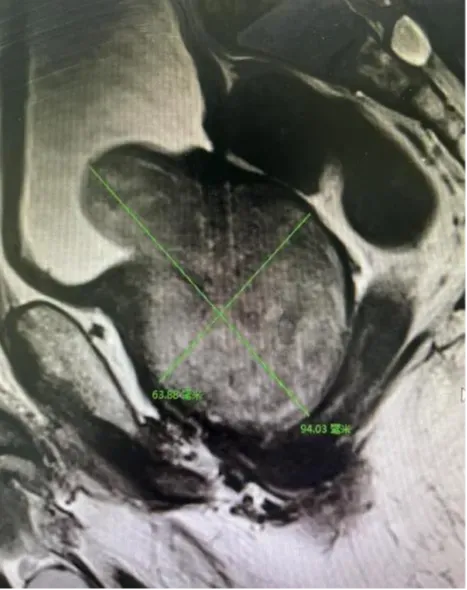

为解决排尿困难问题,两名患者均慕名前往延安市中医医院泌尿外科郭巍主任门诊求助。郭巍主任详细询问病史、完善相关检查后,给出了明确诊断——两人均为巨大体积前列腺增生。检查结果显示,张某的前列腺体积约221ml,是正常前列腺体积(约15ml)的15倍;李某的前列腺体积约186ml,是正常前列腺体积的12倍。